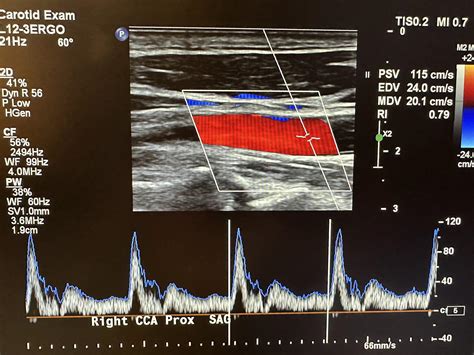

An ultrasound of neck arteries, also known as a carotid ultrasound, uses high-frequency sound waves to create images of the carotid arteries in the neck. These arteries supply blood to the brain, and any obstruction or narrowing can significantly impact brain function. The procedure is painless and typically takes about 30 minutes to complete. It involves the use of a transducer, a device that emits sound waves and captures the echoes as they bounce off the arteries. The resulting images are displayed on a monitor, allowing the technician to assess the condition of the arteries.

The results of an ultrasound of neck arteries are interpreted by a radiologist or a vascular specialist. The images and measurements obtained during the procedure provide valuable information about the condition of your arteries. Key factors that are assessed include:

• Blood Flow: The speed and volume of blood flow through the arteries help to identify any restrictions or obstructions.

• Artery Diameter: Measurements of the artery diameter can detect narrowing or dilation, which may indicate underlying conditions.